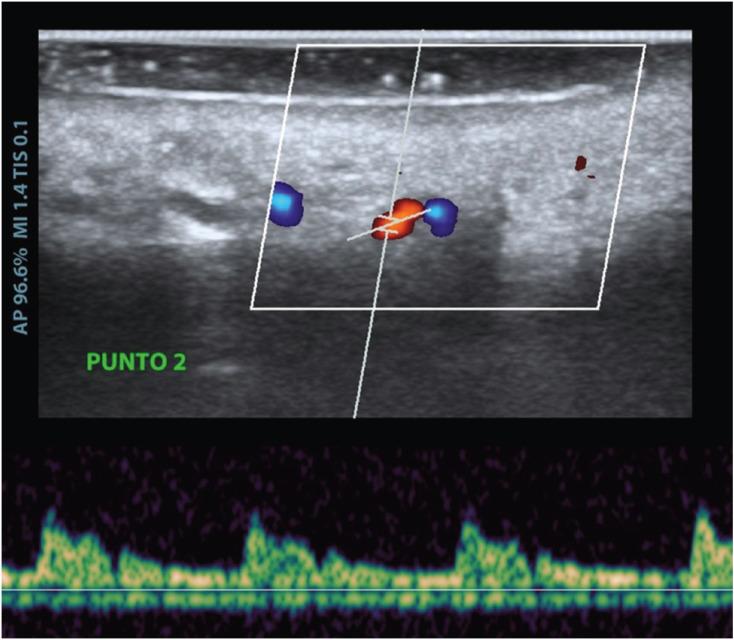

A pilot case series study was performed in a private clinic during February 2020. The scans were performed with a Mindray® M9 ultrasound machine (Mindray North America, NJ, USA) coupled to an L16-4Hs® hockey-type angled probe. For each participant, the arterial path and thickness of the palatal fibromucosa were determined at 5 different points.

2020年2月在一家私人诊所进行了一项初步病例系列研究。扫描使用迈瑞®M9超声诊断仪(迈瑞北美公司,美国新泽西州),配备L16 - 4Hs®曲棍球型角度探头。对于每位参与者,在5个不同点确定腭动脉路径和腭纤维黏膜的厚度。

共纳入6名志愿者(3名男性和3名女性),平均年龄39.2(±16)岁。虽然纤维黏膜厚度沿前部区域减小,但从牙骨质釉质界到动脉位置的距离通常在尖牙位置之前保持不变,在该位置发现动脉靠近牙齿。

彩色多普勒超声可准确确定动脉位置并测量腭纤维黏膜的厚度。这将有助于选择最佳的移植取材区域,以避免因血管切断导致的出血并发症。硬腭、多普勒超声检查、诊断、结缔组织移植。